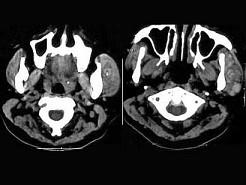

问题 女,14岁,发现左侧耳前肿大三月余,PE:左颊部耳前弥漫性隆起,无压痛,CT如图所示,最可能的诊断是()

选项 A.神经纤维瘤 B.动静脉畸形 C.蜂窝织炎 D.慢性炎症 E.海绵状血管瘤

答案 E